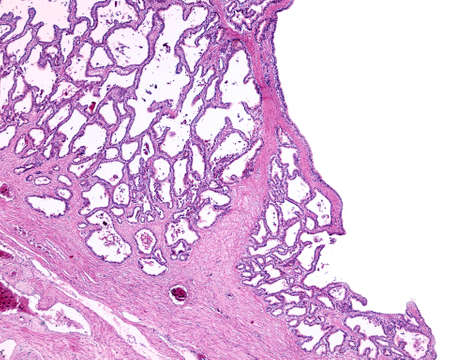

Bowen's Disease Tumor under the microscope 100x